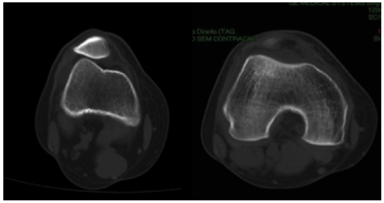

Knee radiograph evaluation (Figure 1 & 2) demonstrated a trochlear groove angle > 145º and type III patella according to the Wiberg classification as well as a crossing sign; there were no arthritic changes and no patella alta or baja; CT scan (Figure 3) showed femoral trochlea dysplasia, normal TT-TG, patella external translation and patella chondromalacia; MRI had the same findings as the CT and reported normal menisci and ligaments.

Figure 3 Knee axial CT scanning; Patella tilt and translation (left) and type a trochlear groove dysplasia (right).

At 2 years follow-up the patient has just residual complaints in her activities of daily living, returned to sports with no major limitations or complaints. She had no episodes of significant pain and swollen knee. The physical examination repeated at follow-up consults showed no major instability, with less than 50% lateral translation, absent pain with patella manipulation and facet palpation. The Lysholm score was 90 and Subjective IKDC score was 87. Post operative CT scan showed aligned patella (Figure 6). The patient is very satisfied with the surgical outcome until this date.

Figure 6 Postoperative knee axial CT scanning, demonstrating patella centered in the trochlear groove, with no tilt.